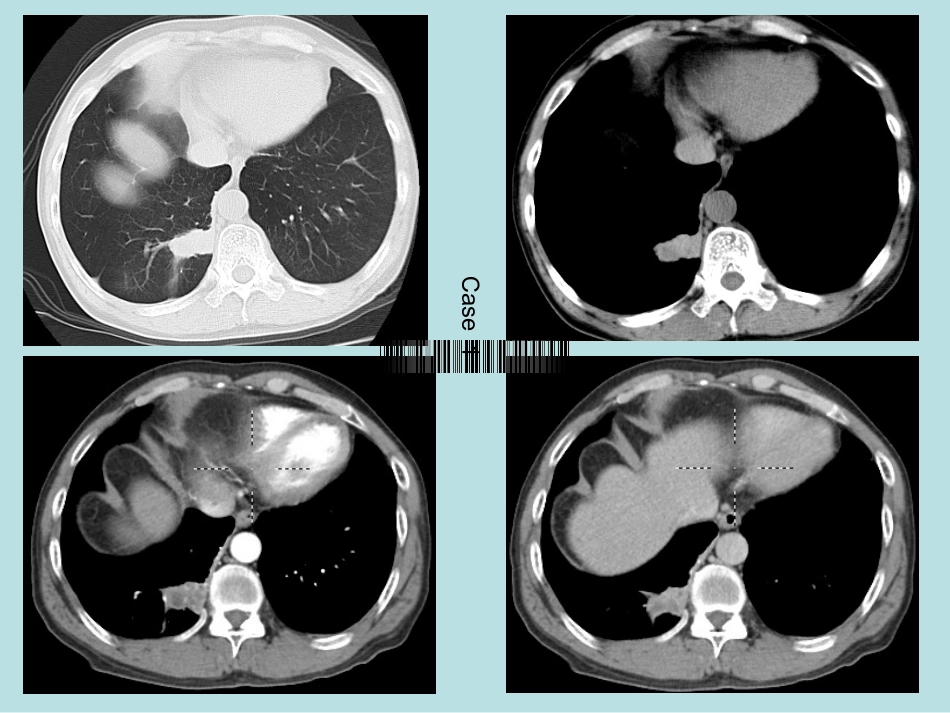

Case1患者,男,57岁,以“反复咳嗽、痰中带血3月余”为主诉入院。缘于入院前3月余明显诱因出现咳嗽、咳痰,呈阵发性,伴有痰中带血,量不多,偶有胸闷、气促感,活动后加剧,休息后缓解,无畏寒、发热,无盗汗,无消瘦,午后低热,无胸痛、心悸,无恶心、呕吐,无腹胀、腹泻等不适,未予重视,未行诊治,期间上述症状反复发作。Case1Case2•患者,66岁,老年男性,以“反复咳嗽、咳痰半年”为主诉入院。2、入院前半年出现反复咳嗽、咳痰,于福建省宁德市医院查CT提示“前纵膈区占位,考虑胸腺瘤可能性大;右中叶及双下肺炎症”。予以“莫西沙星”抗感染等治疗(具体不详)后,于外院复查CT“右肺病变吸收不明显”,其咳嗽咳痰、胸闷气促症状无明显好转,未再规则治疗;查体:体温36.5℃,血压130/80mmHg,双肺呼吸音粗,双下肺可闻及湿性啰音Case3患者庄后彬,男性,65岁,以“咳嗽、咳痰、发热6天”为主诉入院。2、缘于入院前6天“受凉”后出现咳嗽,多为阵发性单声咳,咳嗽不剧,非刺激性,非犬吠样咳嗽,伴咳痰,痰脓黄,量多,明日10-20口,不拉丝,无咳铁锈色痰,伴鼻塞、流涕、发热,体温最高37.5℃,无胸闷、胸痛、呼吸困难,无咯血,无畏冷、寒战,无头晕、恶心、呕吐,无消瘦、盗汗、午后低热,自服“希刻劳、贝莱”等治疗2天后鼻塞、流涕明显好转,体温降至正常,咳嗽、咳痰无明显好转,遂就诊我院,门诊查“血常规示WBC13.58×109/L,N74.9%;肺部CT平扫示左肺炎症,左肺门及纵膈多发淋巴结肿大”,考虑“肺部感染”,予“拜复乐抗感染、愈美片止咳”等治疗,咳嗽、咳痰好转,痰粘白,量少,易咳出,为进一步治疗,门诊拟“肺炎”收入院。Case4患者,女性,68岁,以“发现右上肺病变4天”为主诉入院。入院前4天于我院体检查“肺部CT平扫示:右肺上叶见多发结节状密度增高影,周围密度高,中间密度低,与胸膜关系密切;主动脉及冠状动脉硬化”。无明咳嗽、咳痰,无气促喘憋、呼吸困难、咯血及夜间盗汗,无心悸、胸闷、胸骨后痛。无畏冷、寒战、发热,无腹痛、腹泻、头晕,无皮肤巩膜发黄、尿急、尿痛,无双下肢水肿总结•CT对肺内结节的诊断价值主要有三这方面:1、病变存在的诊断。2、病变定性诊断。3、病变定位诊断。4、病变定量诊断,即:肿瘤分期诊断。•对肺内结节定性诊断应从三方面入手,首先是观察病变内部结构,其次为病变边缘特征,最后是观察局部支气管改变。•1.病变大小和倍增时间病灶直径等于或小于3cm者称为结节,而大于3cm者称为肿块。倍增是指体积增大一倍,简略算法是直径增加1.25倍则体积增大一倍,其所需时间为倍增时间。肺癌必然长大,虽然在癌块较小时生长缓慢,但当直径超过3cm时就可能发展迅速。因此影像学动态观察非常重要。如为新出病灶或较过去增大,应高度怀疑恶性可能。如肺内结节在30天内体积加倍多为炎症,而490天以上无变化可考虑良性。•2.病变的外形和境界主要有分叶征、细小毛刺征、胸膜凹陷征、血管集束征。•3.支气管改变支气管壁增厚是早期改变支气管狭窄支气管梗阻和肺不张